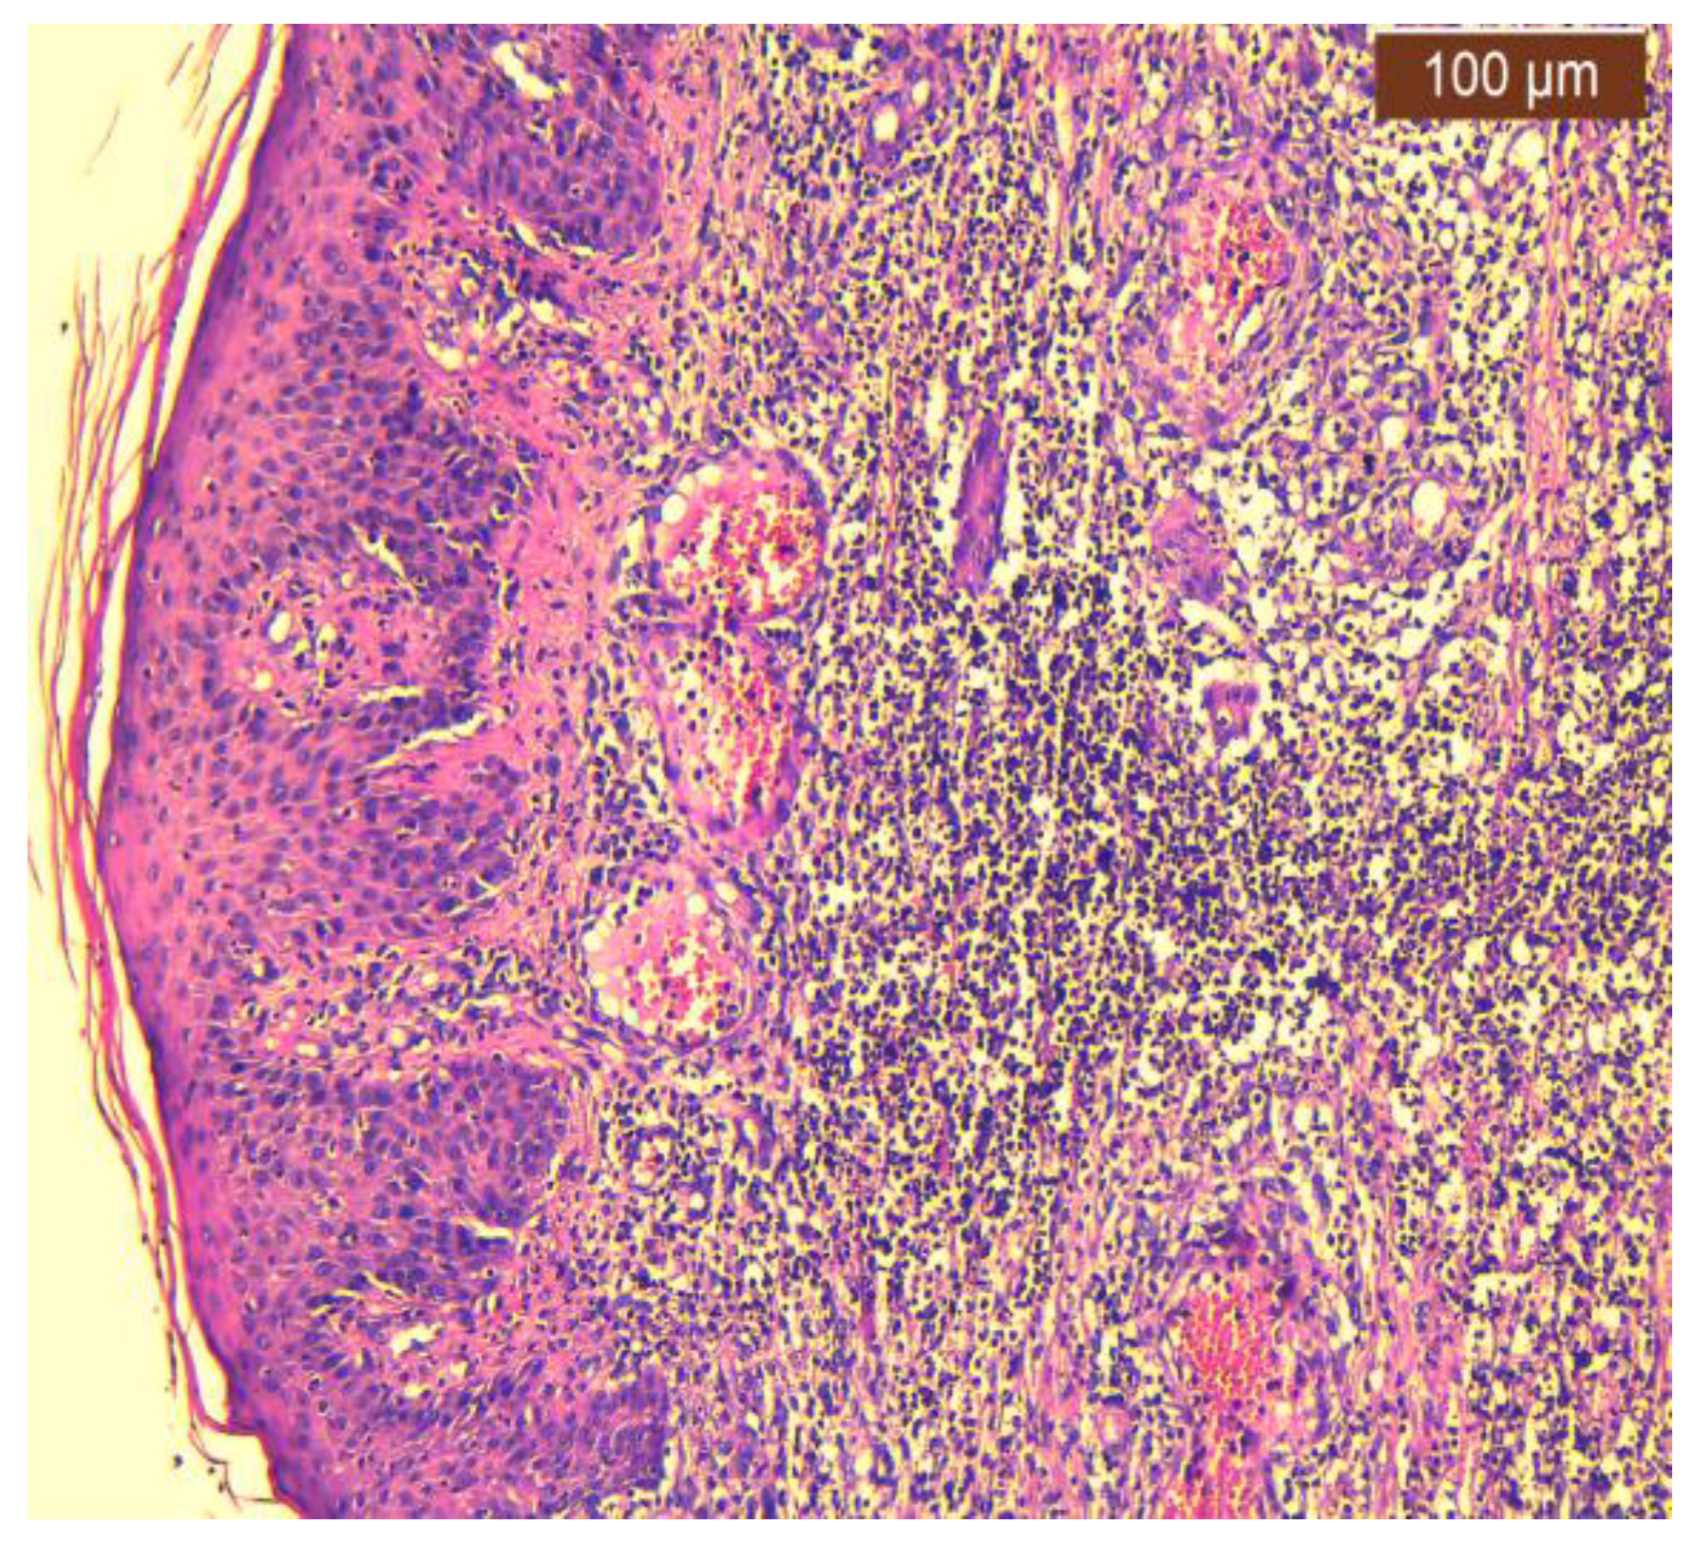

2.2. Histopathology Findings